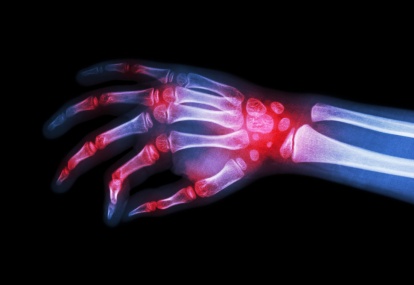

Amyloidosis is a disorder of protein folding, where structurally diverse precursor proteins adopt an abnormal but common fibrillar structure, ultimately damaging tissue structure and leading to organ dysfunction. Depending on the dominantly affected organ, a patient may be referred on to a...